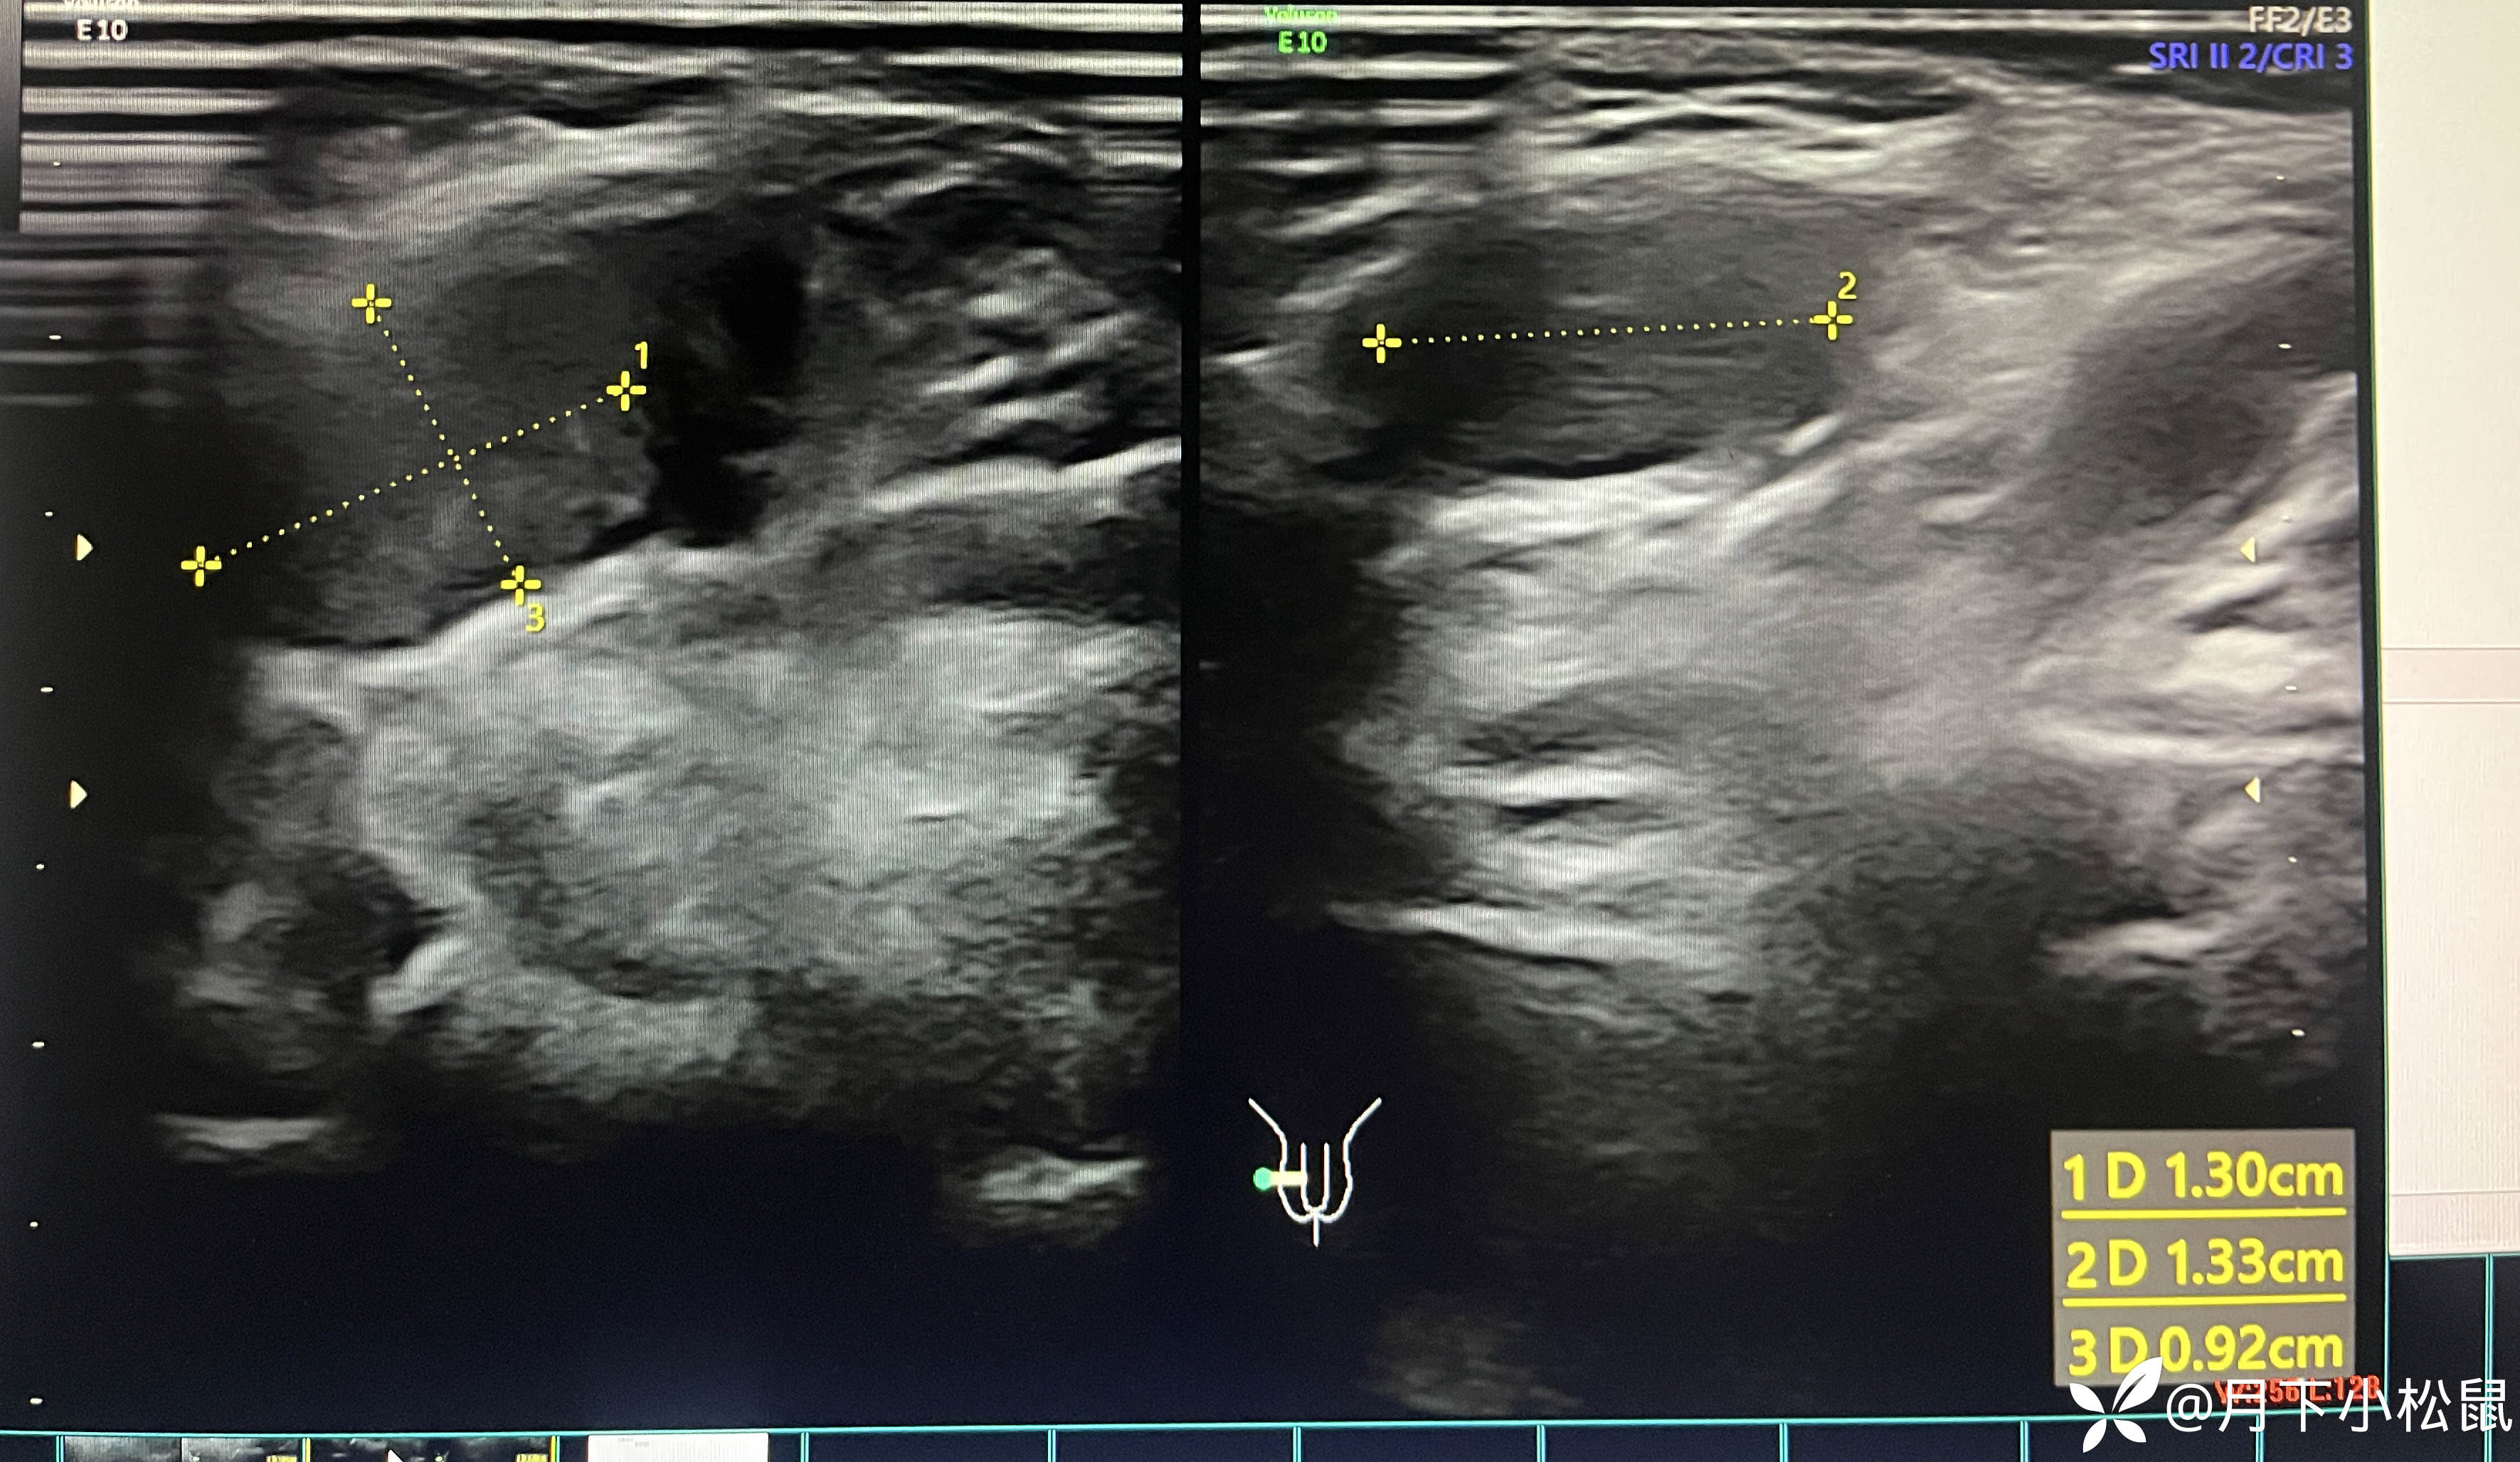

给开了B超,申请单上面写了详细的体格检查内容,同时嘱家属在做B超时一定和做B超的医生说仔细看看蛋蛋。

腹部B超检查报告回报示:

报告: